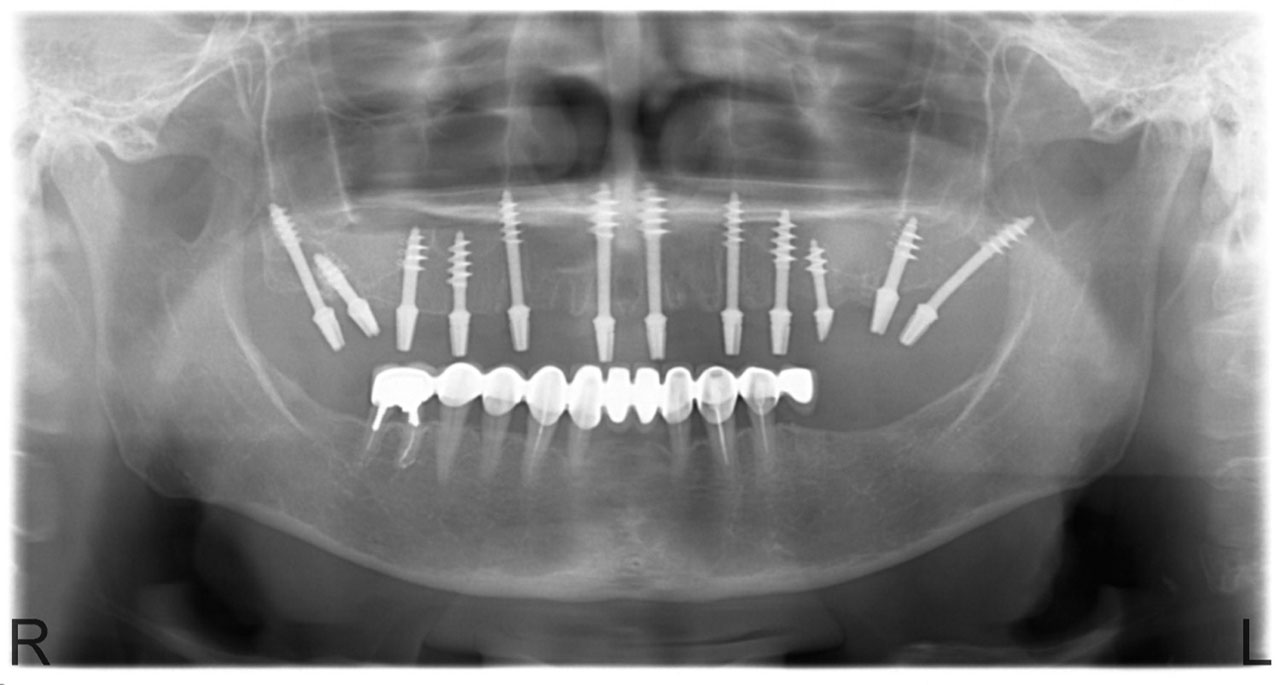

Esetbemutató

• esettanulmany-01

Implantáció előtt, gyulladt, törött fogak.

• esettanulmany-03

Imlantáció után,bal oldalon már a végleges hidakkal, jobb oldalon még csak az implantátumok.

• esettanulmany-14

Alsó- felső fogatlan állcsont teljes implantációs helyreállítása.